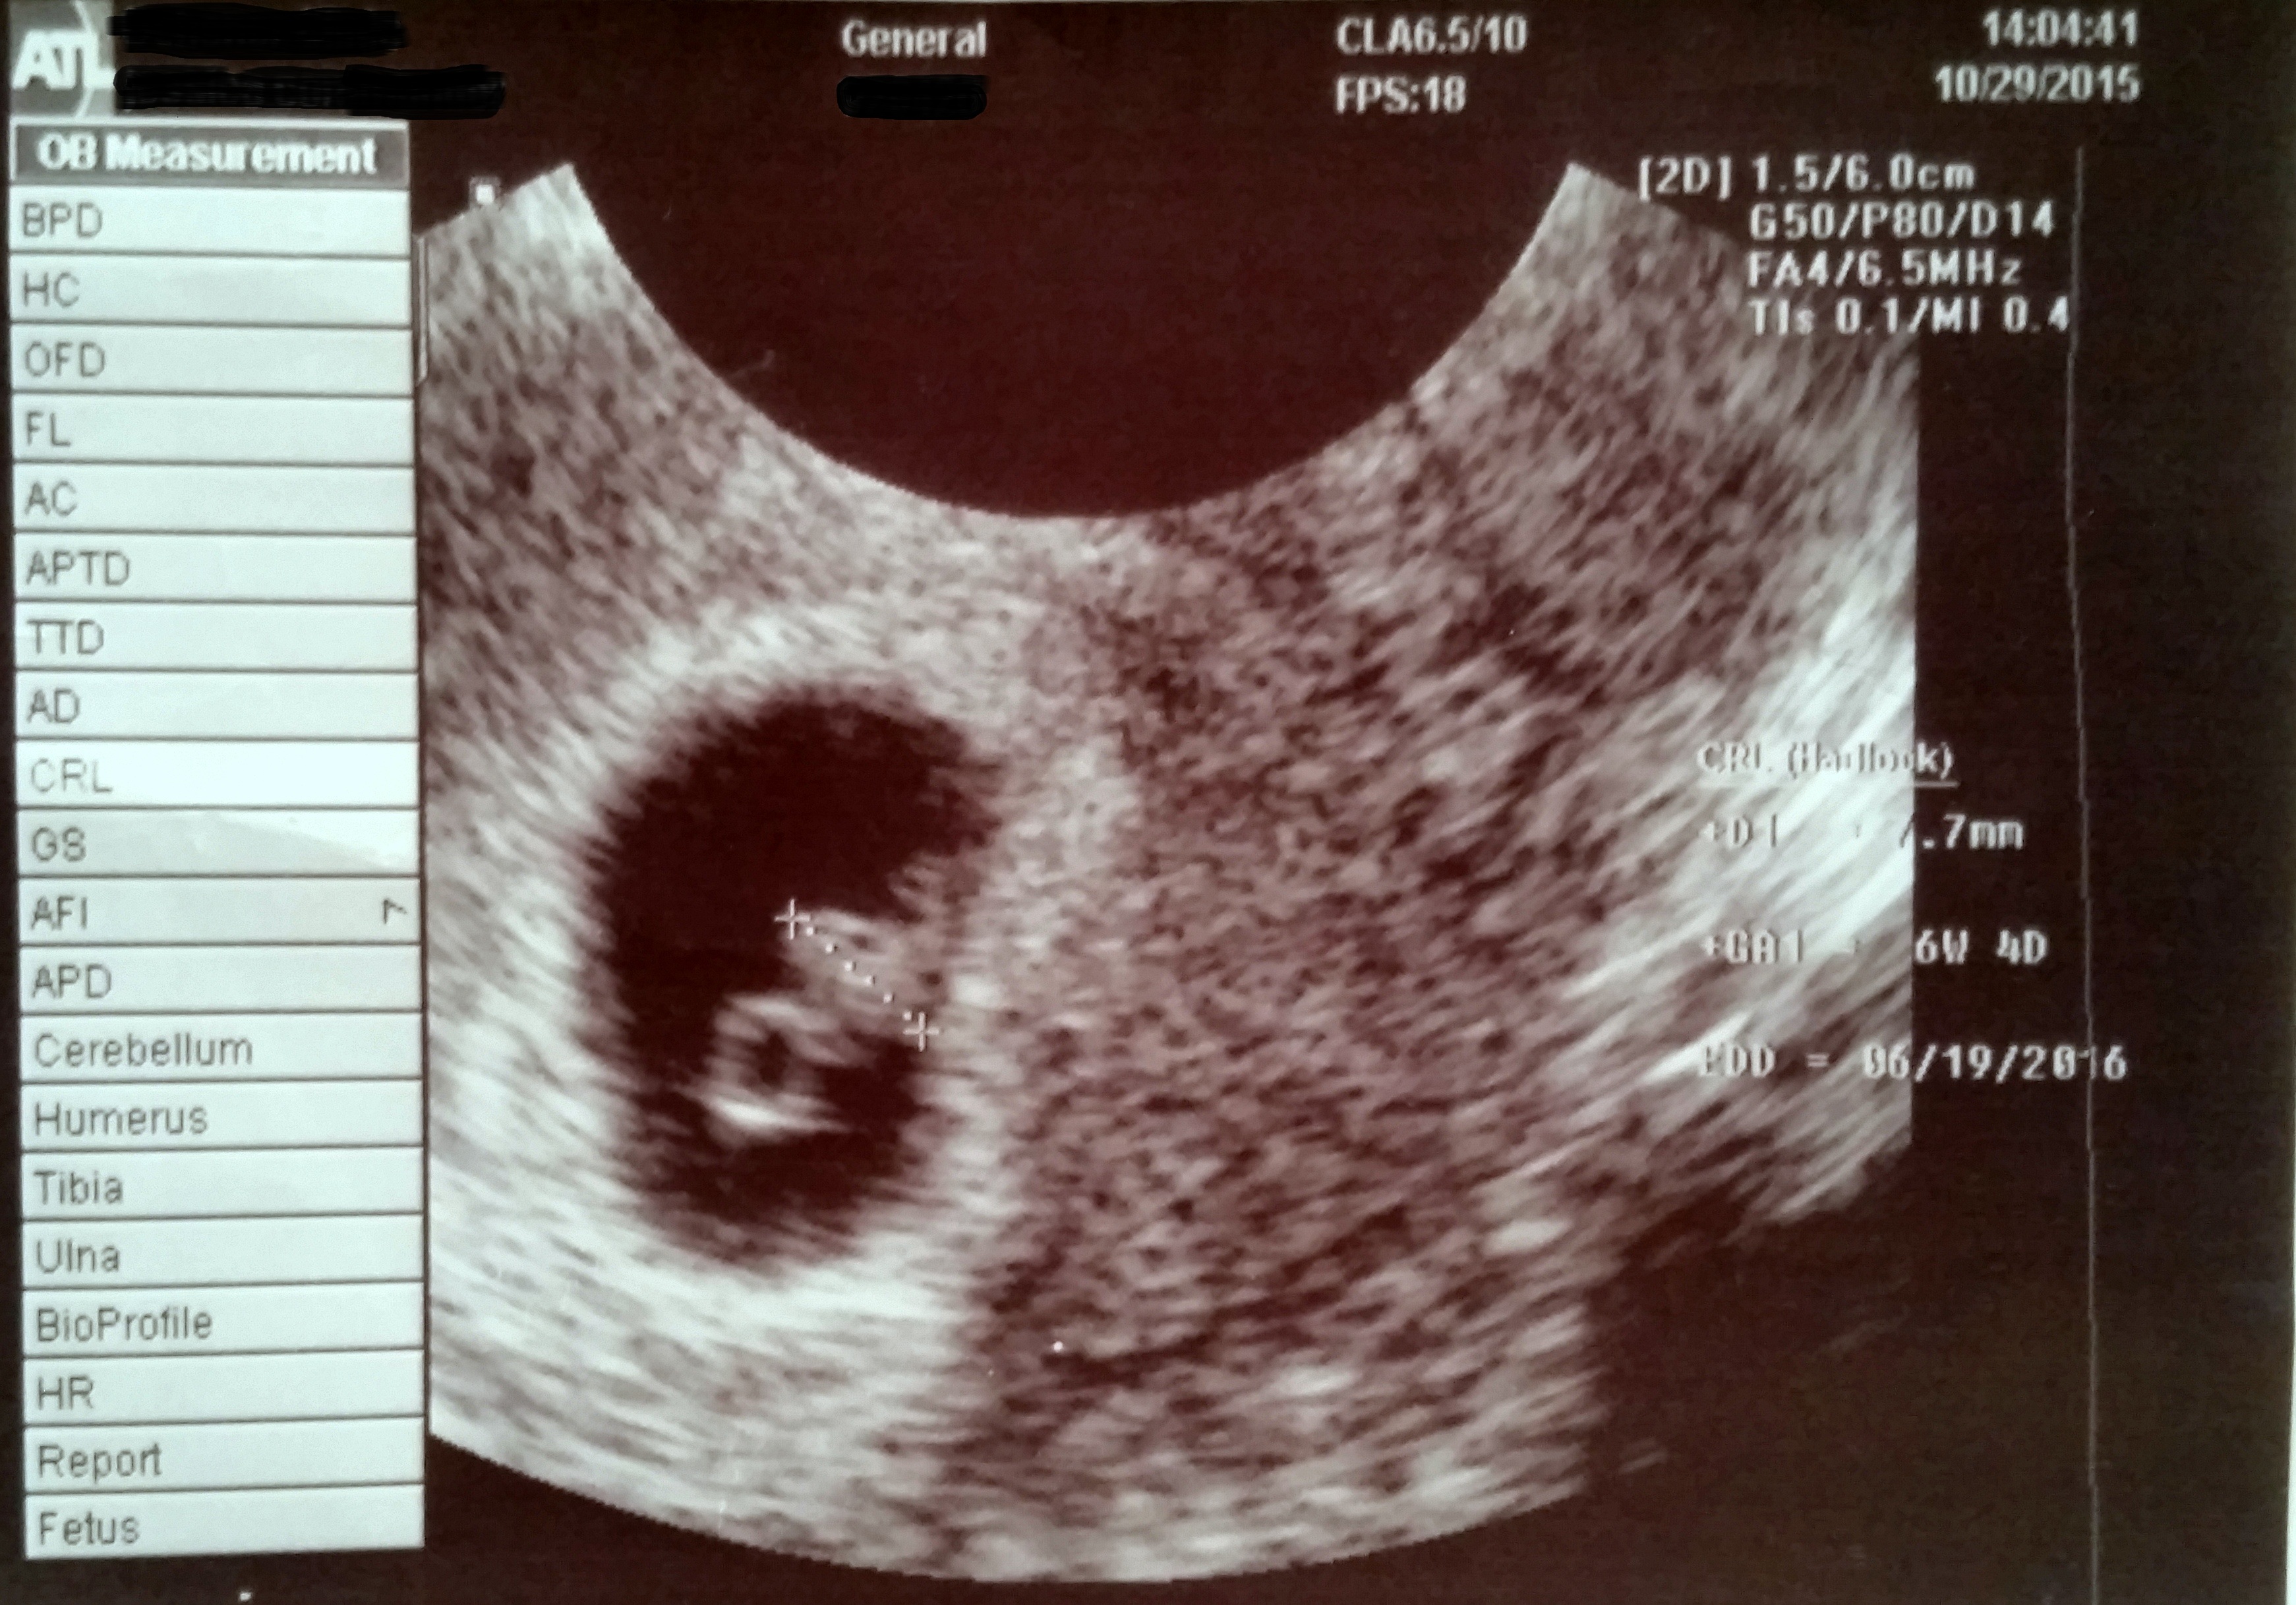

Had my 1st appt today and im 7w2d today. Due June 19th. Had a Mc last year on Oct 24th and found out this year I was prego on Oct 23rd. This will be our first child and we were so excited and shocked to see the baby and hear the hearbeat.